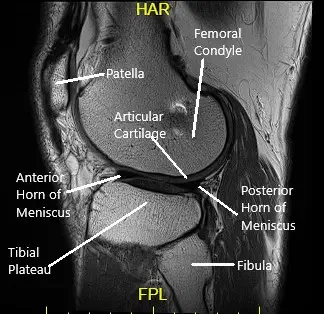

Le realizaron una resonancia magnética que mostró desgarros del menisco medial en la unión meniscocapsular y la unión posterior cuerno-cuerpo. Hubo pérdida de cartílago tricompartimental.

Vista de la rodilla izquierda por resonancia magnética sagital.